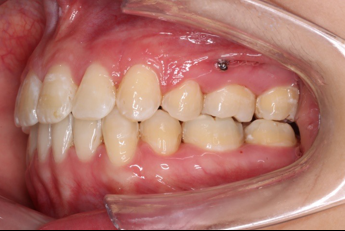

• 磨牙,尖牙I类关系,中线齐

• 上下牙列中度拥挤

• 上下前牙唇倾

IntraoralExamination(2016-08.31,Wu)

2018.11.14  术后磨牙尖牙I类关系,中线齐,覆合,覆盖正常